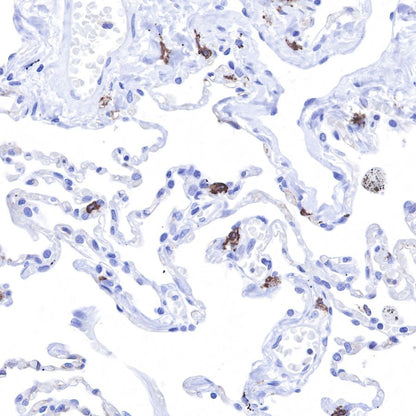

IHC shows positive staining in paraffin-embedded human lung cancer.

Anti-CD117 antibody was used at 1/1000 dilution, followed by a Goat Anti-Rabbit IgG H&L (HRP) ready to use.

Counterstained with hematoxylin.

Heat mediated antigen retrieval with Tris/EDTA buffer pH9.0 was performed before commencing with IHC staining protocol.